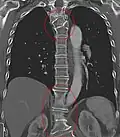

Several congenital block vertebrae in the transition from the thoracic to the lumbar spine and hemivertebrae. -